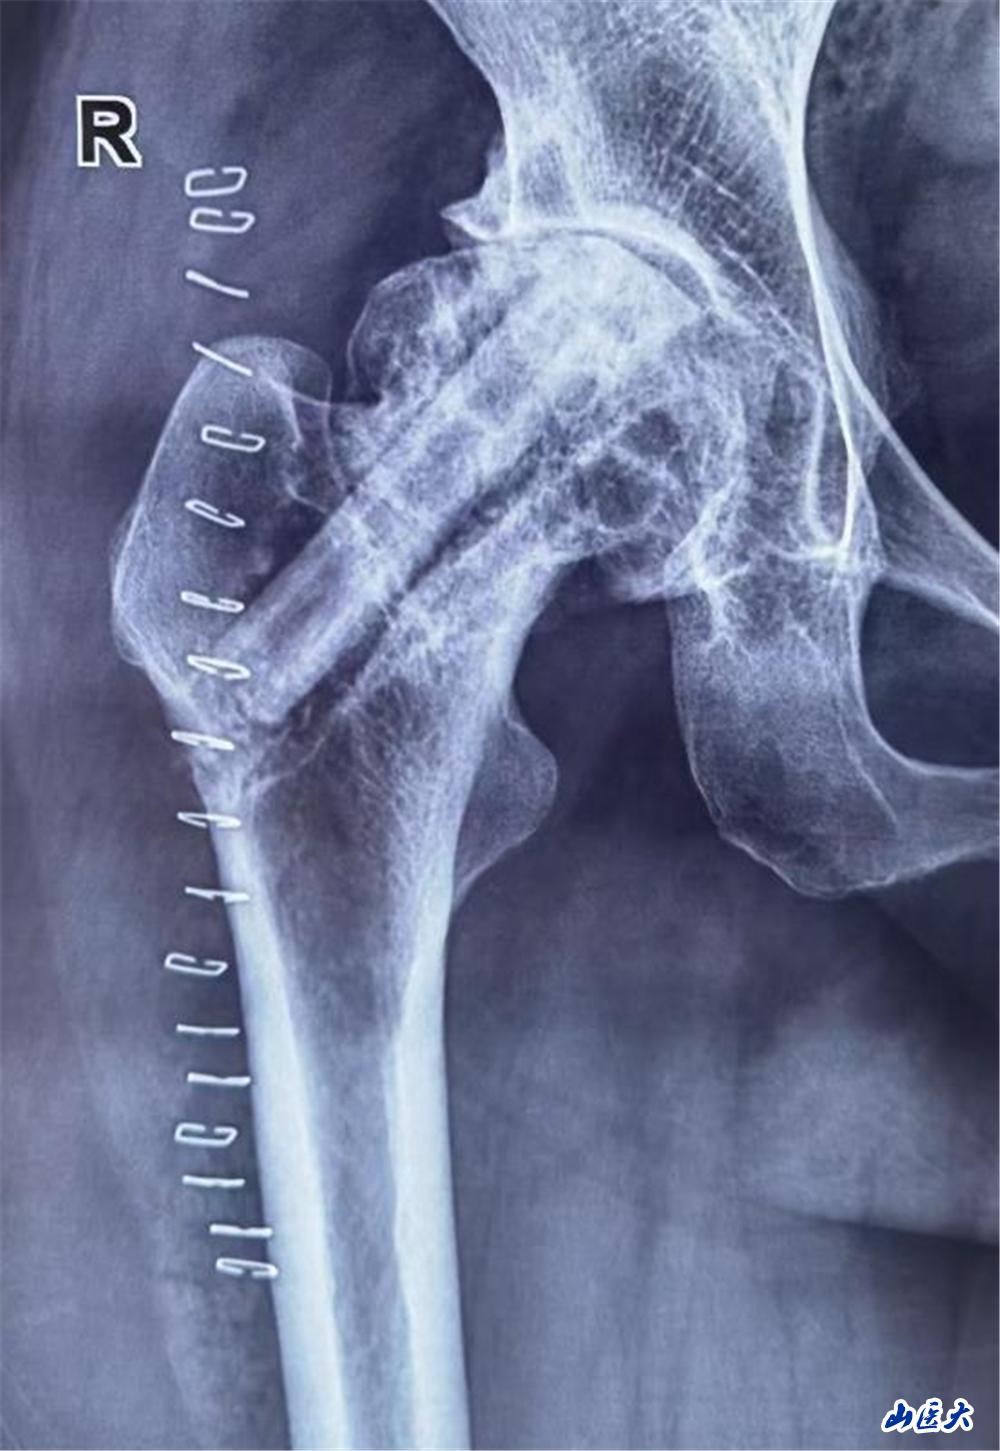

陳大姐飽受股骨頭壞死折磨3年,近一個月疼痛加重,行走困難。面對患者強烈的保髖愿望,醫療團隊術前通過影像學檢查及血管評估,精準分析患者股骨頭壞死范圍及血供情況,為其量身定制了“帶血管蒂的腓骨瓣移植”手術方案。這一術式能重建股骨頭血運,延緩甚至避免關節置換,但對醫生的顯微外科技術要求極高。

手術當日面臨巨大挑戰,醫療團隊需在患者腓骨處截取長約6cm的帶血管骨瓣,并在顯微鏡下將細如發絲的旋髂外側動脈與股骨頭供血血管吻合。5個半小時的奮戰,每一步都考驗著團隊的默契與技藝。